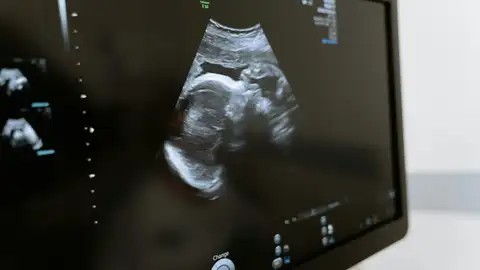

En los últimos días, el debate sobre el aborto ha vuelto a ocupar la agenda política en España. Entre los argumentos utilizados en contra de la interrupción voluntaria del embarazo, algunos sectores han vuelto a mencionar la existencia del llamado "síndrome post aborto", un supuesto cuadro de trastornos psicológicos que aparecería tras la práctica. Pero, ¿qué dice la ciencia al respecto?